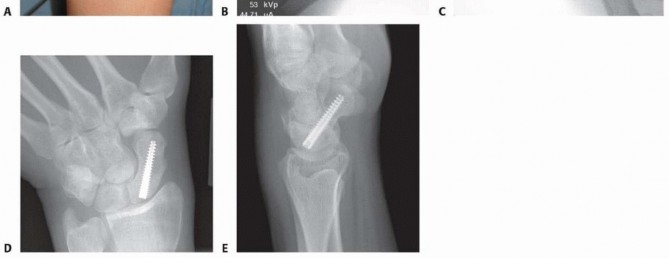

### TECH FIG 2 • A-C. Before screw insertion, the position of the Kirschner wire must be changed from its position used for arthroscopy. The Kirschner wire should be driven from volar to dorsal until the distal end lies just beneath the articular surface of the scaphoid. D,E. Screw fixation of minimally displaced scaphoid fracture via the dorsal percutaneous technique. The screw tip should rest within 1 to 2 mm of the distal cortex. Excellent compression should be obtained with this technique. The proximal fragment, which is now freely mobile, is reduced manually using the Kirschner wire joysticks. Once the fracture is reduced, the central guidewire is driven from volar to dorsal into the proximal fragment, securing it in place ( TECH FIG 3D).24, 25 The guidewire is further advanced from volar to dorsal until its distal tip is just within the subchondral bone of the distal articular surface. This allows for measurement of the screw length as previously described.

Insert an Acutrak 2, mini-Acutrak 2 screw (Acumed, Beaverton, OR), or other cannulated headless compression screw of appropriate length (at least 4 mm shorter than the measured scaphoid length) to within 1 to 2 mm of the distal surface. The tip of the screw should not penetrate the distal surface, and the proximal end of the screw should rest 2 mm deep to the proximal articular cartilage ( TECH FIG 2D,E). Confirm satisfactory screw position and fracture reduction with fluoroscopy. The screw should be inserted down the central axis of the scaphoid. If any doubt exists, use the arthroscopic portals to confirm that the screw is buried in the scaphoid. The 3-4 portal and the radial midcarpal portals provide the best view to ensure that the fracture is adequately reduced and that there is no violation of the midcarpal joint. ### Displaced Scaphoid Waist Fracture Insert two percutaneous 0.062-inch smooth Kirschner wires dorsally into each fragment perpendicular to the long axis of the scaphoid to be used as joysticks to reduce the fracture ( TECH FIG 3A,B). Position the wrist as previously described. The guidewire from the Acutrak 2 system (or the surgeon's chosen system) is inserted from proximal to distal, starting dorsally and aiming for the central axis of the distal fragment. The guidewire is driven through the distal fragment and out through the volar skin of the hand. The protruding tip is then pulled volarly until the wire is only in the distal fragment ( TECH FIG 3C).24, 25 115